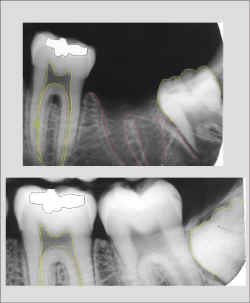

Identificação Humana por Comparação Computadorizada de Imagens

Radiográficas Dentárias